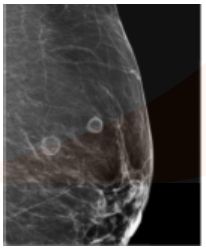

The following imaging on mammography represents a _____

Mammographic calcifications can be associated with benign conditions such as _____ (fibrocystic change) and fat necrosis